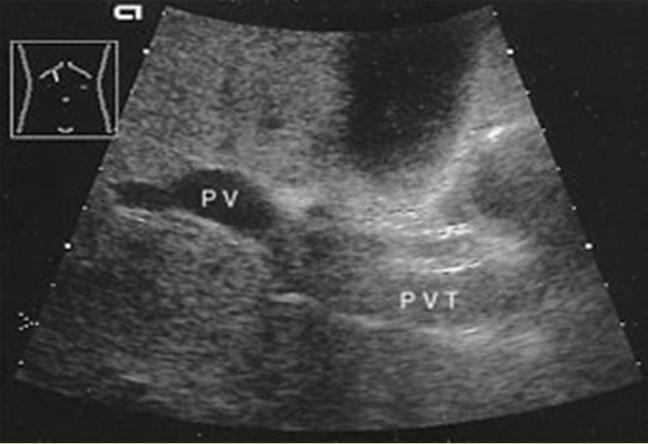

What is Portal Venous Thrombosis?

Portal Venous Thrombosis

What is the sonographic appearance of Portal Venous Thrombosis?

Portal flow absence

echogenic thrombosis

Worm-like

structures near porta hepatis

What are the presenting symptoms of Portal Venous Thrombosis?

vague and non-specific